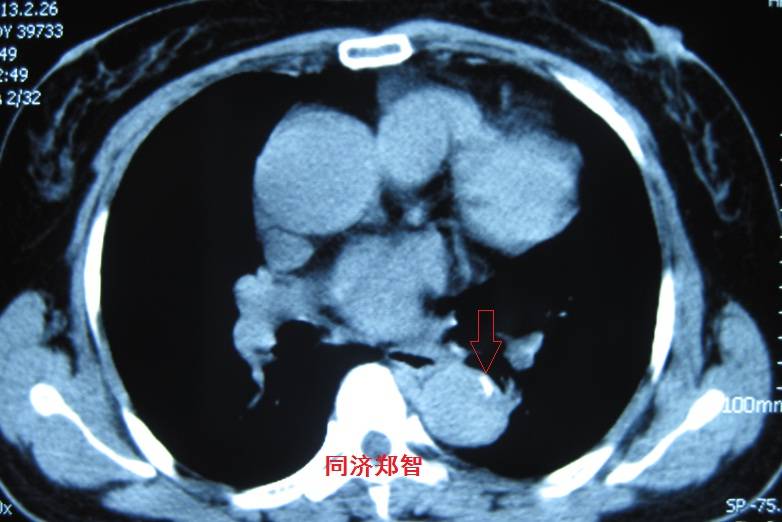

病例二

胸部平扫CT提示升主动脉增宽(红色星形标记),CTA证实A型主动脉夹层伴升主动脉夹层动脉瘤形成。